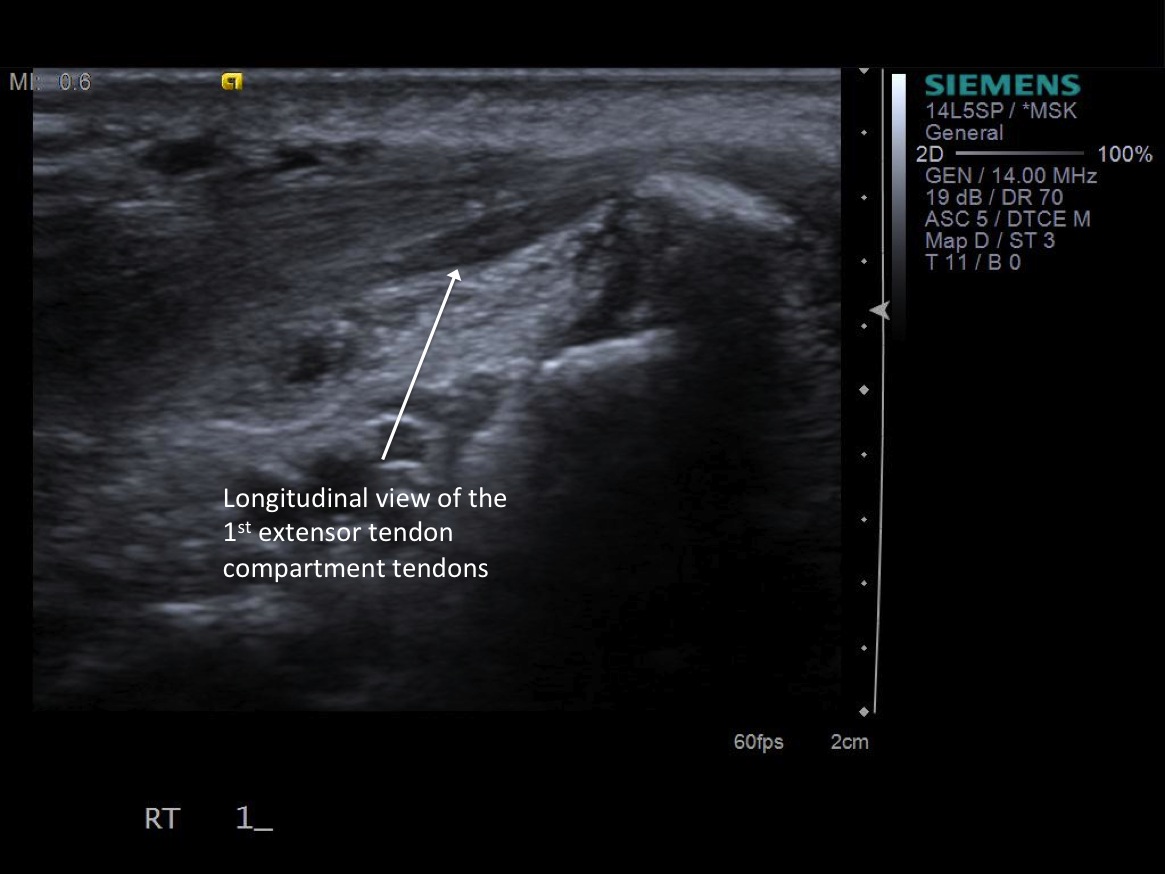

• probe: 14Mhz hockey stick probe

3. Place probe in short axis over first comparment extensor tendons-- Extensor pollicis brevis and abductor pollicis longus. description description